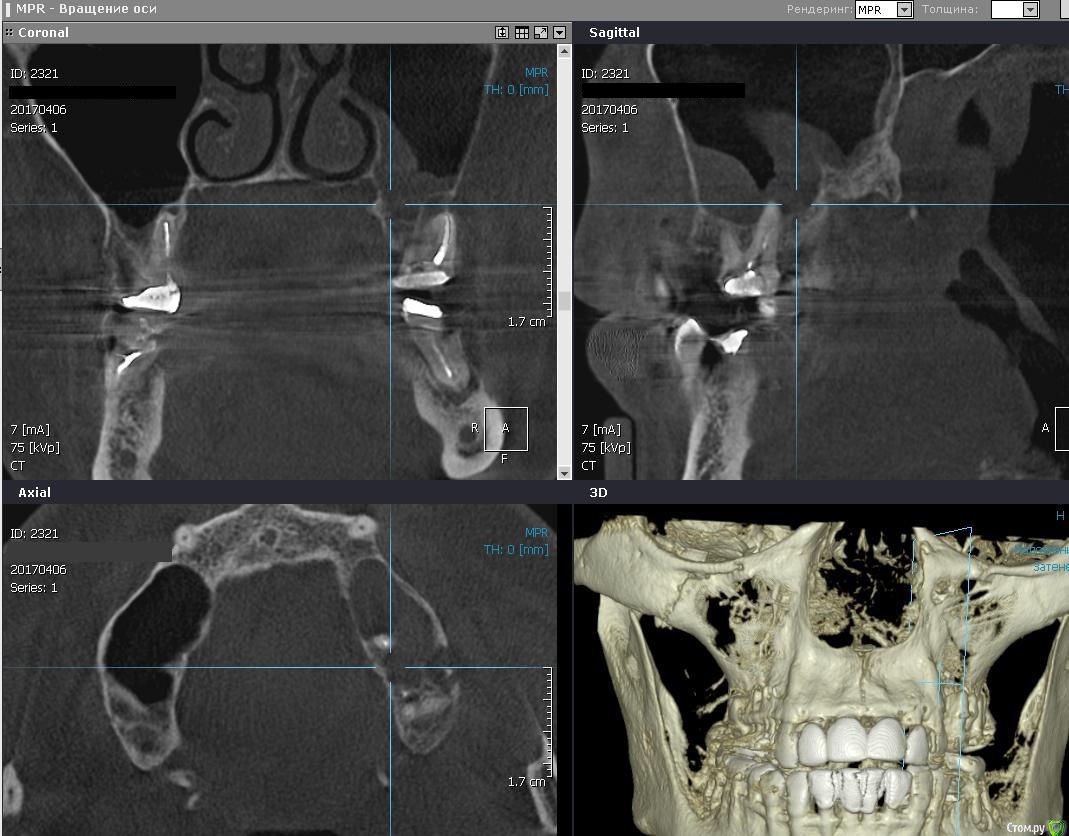

Romanson Опубликовано 10 апреля, 2017 Поделиться Опубликовано 10 апреля, 2017 Здравствуйте, подскажите как бы вы поступили в такой ситуации? Ничего не беспокоит, на затрудненное дыхание не жалуется.Удалить, отпустить, сделать повторное кт - если все нормально, то делать синуслифтинг, устанавливать имплантанты?Удалить, попытаться сделать пункцию мягкотканного компонента, если есть содержимое то пытаться вылущить оболочку из пазухи?Как действуете в подобных ситуациях? Ссылка на комментарий